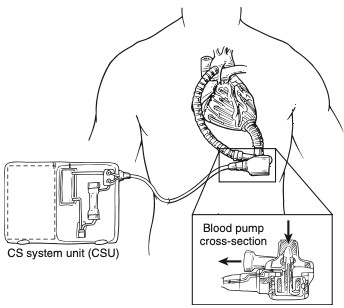

A insuficiência cardíaca (IC) é uma anormalidade da função cardíaca decorrente da inabilidade do coração de atender a demanda…